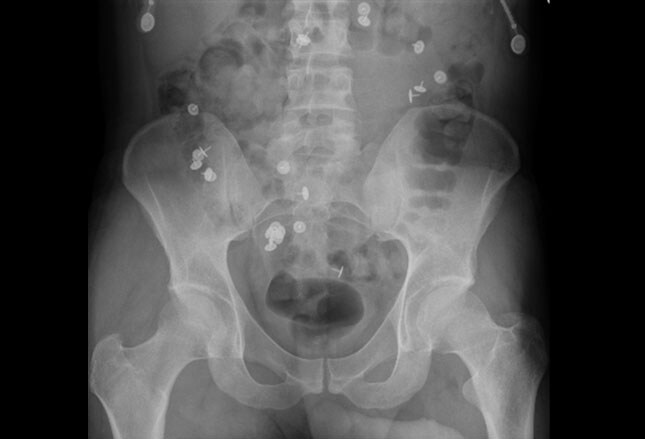

The vast majority of such objects are inserted via the anus and are the result of sexual misadventure . This is usually voluntary although occasionally happens as part of sexual assault/rape . In older men, the objects may be introduced to aid in manual disimpaction for constipation or to massage the prostate .

Intentional ingestion and insertion of foreign objects is a topic that has generated mounting interest among medical professionals over the past two decades . When featured in the literature, it has been typically discussed in medical subdisciplines, such as emergency medicine, surgery, gastroenterology, and urology . However, in-depth exploration of this multidimensional phenomenon in the field . . .